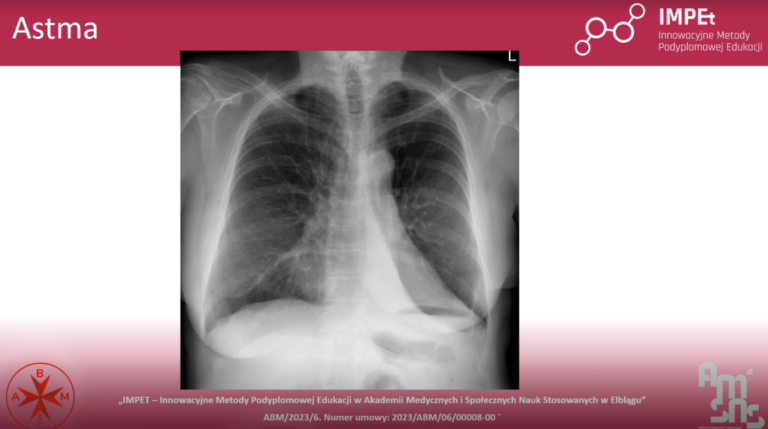

• Diagnostykę chorób, m.in. astmy czy włóknienia płuc,

• RTG klatki piersiowej jako podstawowe badanie obrazowe w pulmonologii.